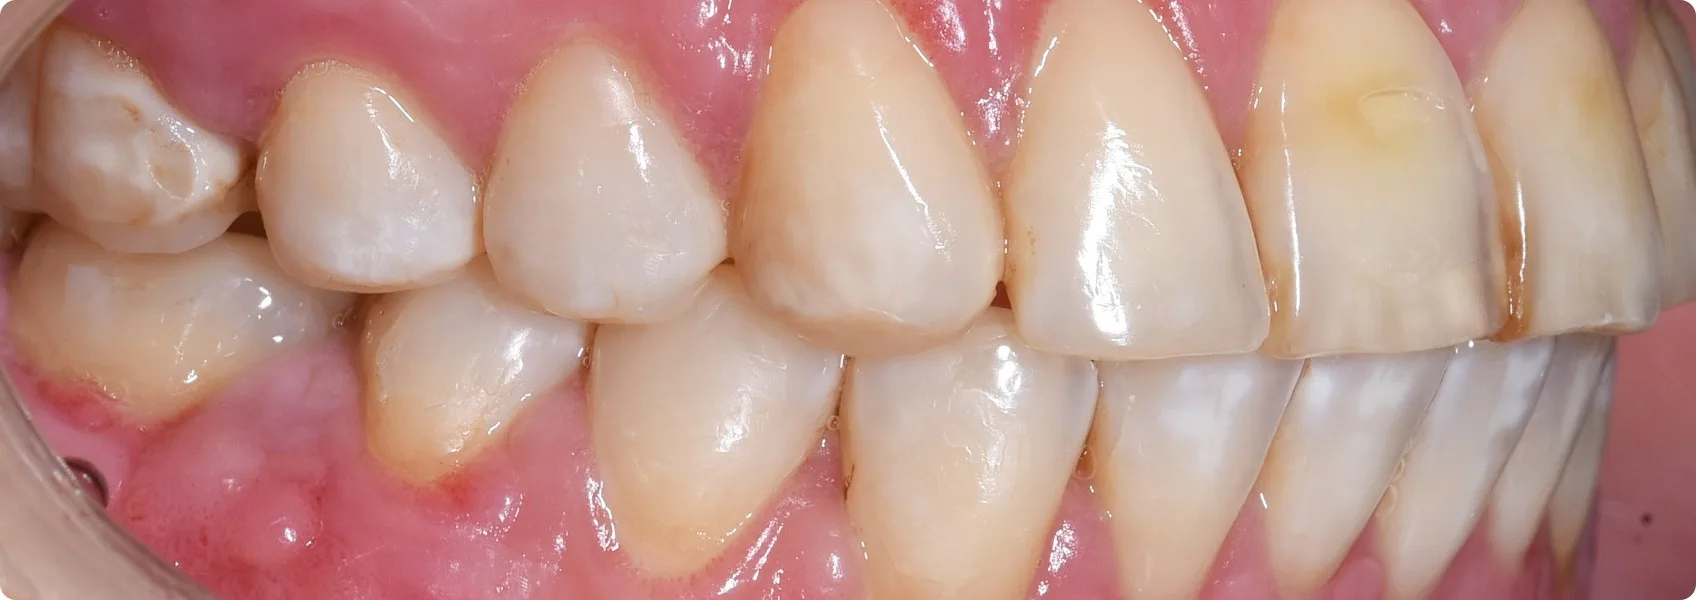

U Pacjentki fluoroza wystąpiła w obrębie zębów górnych oraz dolnych. Do NDC zgłosiła się po zakończonym leczeniu ortodontycznym w innej klinice.

Licówki to cienkie płatki porcelany, które przykleja się do przedniej strony oszlifowanego zęba. Zęby Pacjentki trzeba było jednak wybielić aż o 5 odcieni. Do tego wadliwa budowa szkliwa z fluorozą nie pozwalała na przyklejenie klasycznych licówek (adhezyjnych).

To oznaczało, że licówka musi być większa i grubsza, a oszlifowanie (preparacja) zęba — głębsze. Tylko w takim przypadku kolor będzie satysfakcjonujący, a licówka się nie odklei.

Wybór padł na licówki o poszerzonym zasięgu — tzw. korony częściowe.

To specjalny typ licówek, które pokrywają większą część zęba niż te klasyczne. Nie tylko przednią powierzchnię, ale również fragmenty powierzchni żujących, siecznych lub bocznych. Można je traktować jako „półkorony”, ponieważ łączą estetykę licówki z częściową funkcją ochronną korony protetycznej.